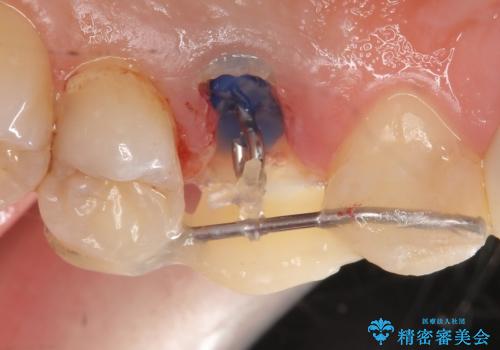

左上4の補綴物を除去したところ縁下歯質だったため、歯牙の挺出を提案し行いました。

挺出終了後は歯肉切除および骨外科により歯周組織を整え、オールセラミッククラウンによる補綴を行いました。

縁下カリエス(歯茎より深い虫歯)の治療について

虫歯が進み歯茎より深くなってしまうと、虫歯を取り残してしまうリスク、樹脂の硬化の妨げ、補綴物の不適合、歯肉炎・歯周病のリスクの増大等様々な弊害が起こり得ます。

そのため当院では歯周外科手術(歯茎を下げる手術)や歯の挺出による、虫歯が歯茎より深いという問題の解決を推奨しております。